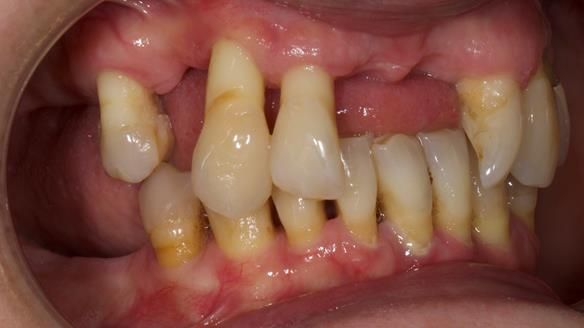

She had previously suffered from generalised periodontitis – stage IV, grade C, currently stable, with reduced attachment across the upper arch.

By the time she came to me, her periodontal condition was stable — but the aesthetics in the upper jaw were very poor.

Dr Syed Abad — my colleague and a Specialist in Periodontics — had successfully stabilised her gum health.

- Her upper jaw had insufficient bone and would have required significant augmentation.

- The financial investment for implant treatment was outside her budget.

- Crucially, Syed had full confidence that I — working with Rowan (my in-house technician) — could provide a first-class removable solution.